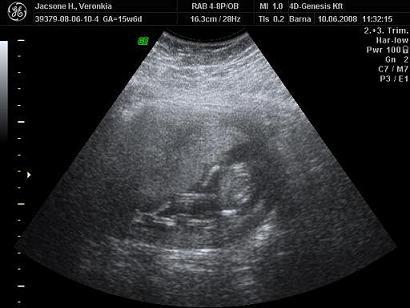

Neked is köszi a választ! Remélem nálunk is elmúlik majd az ellenőrzésre...vagy 25. hétre, mikor megint 4d-re megyek.

A lepényt ultrahangon tudják megnézni, hogy hol tapad. Én a 4D genesist ajánlom nagyon, és a Baross utcába semmiképp ne menj! Az előbbi helyen 10.500ft a vizsgálat, amiben benne van a 30perces vizsgálat, amit egy az egyben dvd-re vesznek, maga a dvd, és egy szép nyomtatott szines kép. Plussz 1500ft-ért kérhetsz egy cd-t is, amire sok képet tesznek, én 53-at kaptam, és a media marktban mind elő is hívattuk.